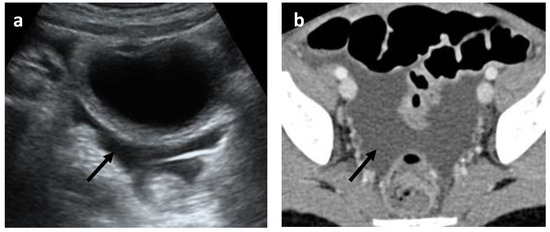

- Abnormalities of the hollow visceral organs, including distension and wall thickening of the gallbladder (Figure 4), stomach, bowel, small bowel (Figure 5A, and urinary bladder (on CT and ultrasound). They were considered thickened if >3 mm. Additionally, the cross-sectional diameter of appendix is considered enlarged if >6 mm (Figure 5B).

- Mesenteric and retroperitoneal lymphadenopathy (Figure 7) with mesenteric lymph nodes considered enlarged if >5 mm in short axis and retroperitoneal lymph nodes considered enlarged if >9 mm in short axis.